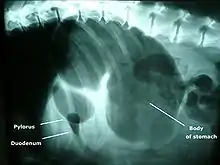

Síndrome da Dilatação-Vólvulo Gástrico (Gastric Dilatation-Volvulus - GDV) é uma deficiência proveniente do mau posicionamento do estômago de cães. Requer pronto atendimento cirúgico e clínico.

torção do estômago